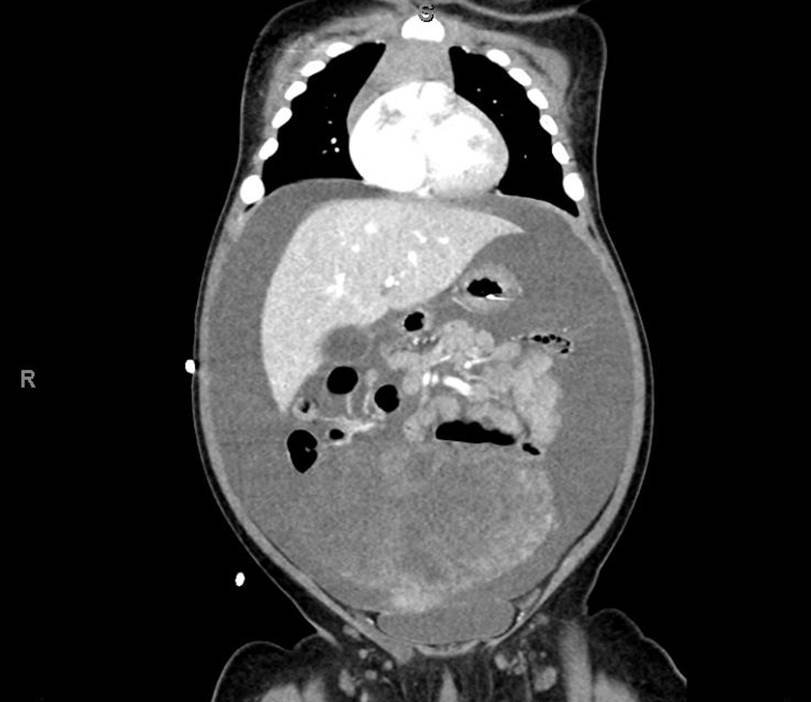

A 5-month-old female presented to the emergency department with worsening abdominal distention and postprandial emesis. Point-of-care ultrasound (POCUS) demonstrated extensive abdominal free fluid with a large, heterogeneous mass in the suprapubic region. This was confirmed on computed tomography (CT) of the abdomen and pelvis. The patient was urgently taken to the operating room for exploratory laparotomy where a ruptured tumor was discovered. The patient was eventually diagnosed with ovarian juvenile granulosa cell tumor. POCUS can be vital in guiding the recognition of rare pediatric conditions in the emergency department and should be considered in patients where there is concern for an acute abdomen.